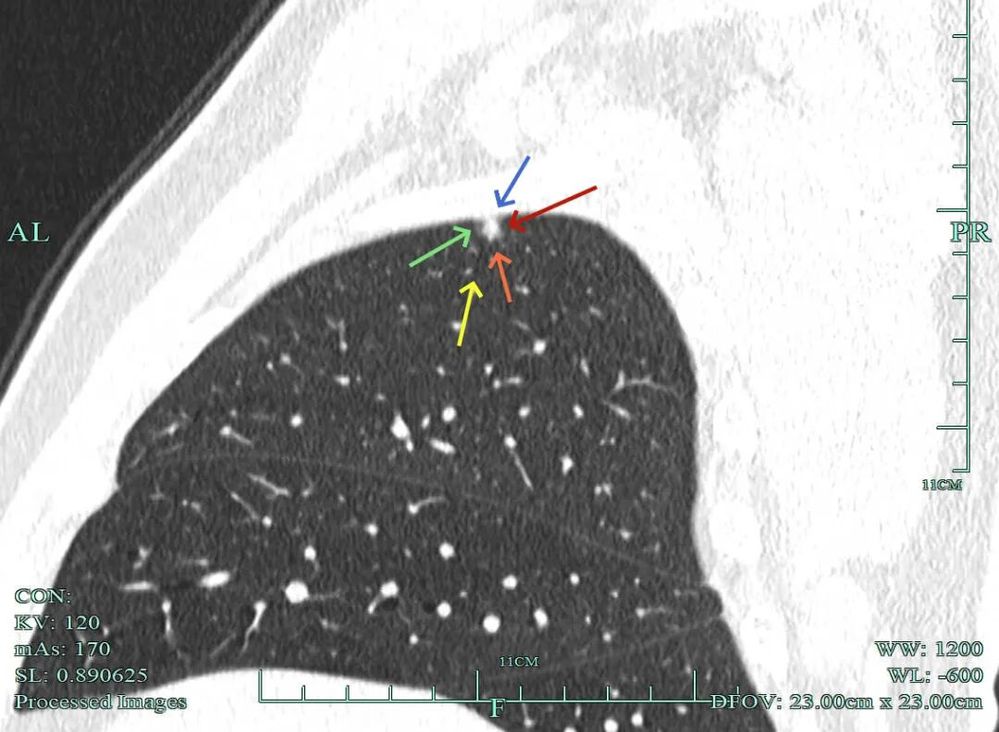

影像展示与分析:

杭州市肿瘤医院影像展示与分析:

右上也有混合密度结节,实性部分缺乏膨胀性与收缩力,磨玻璃成分较淡,也偏糊,但持续存在仍得考虑肿瘤范畴可能性大。

此视角是混合密度,实性为主,贴胸膜近。